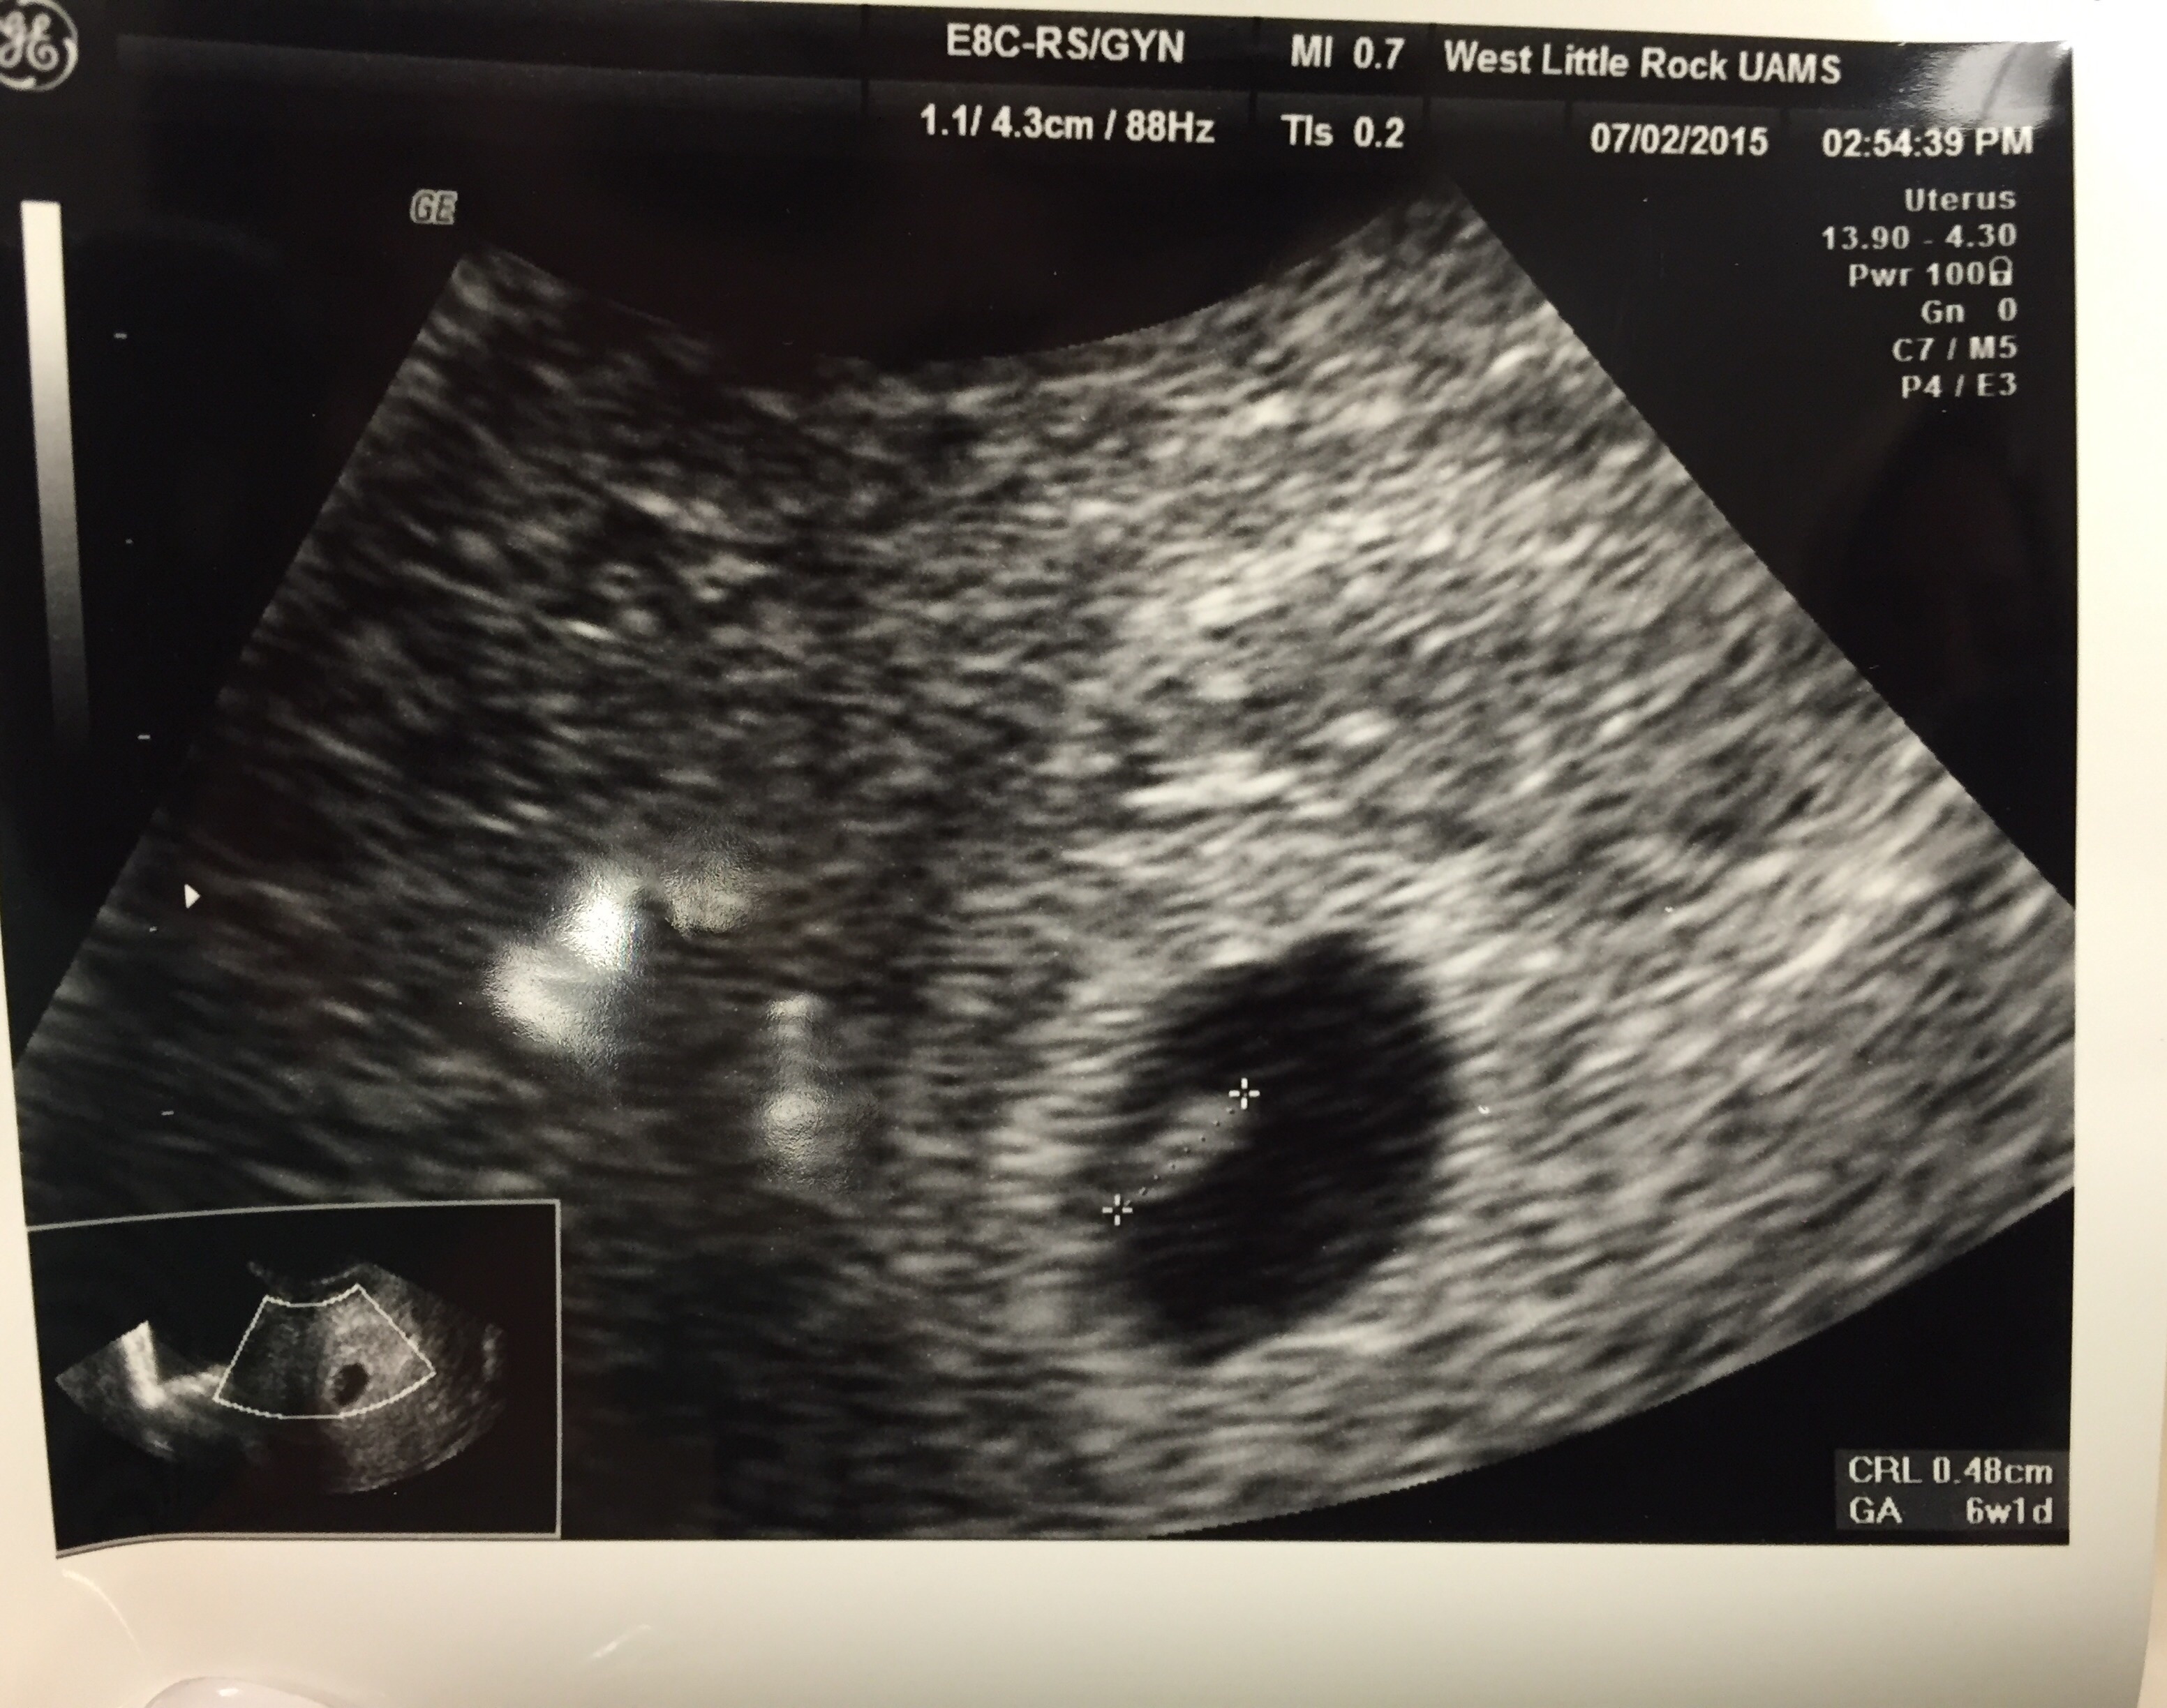

This is my first post, but I am due 2/5/16 with my first little one. Heart rate was 167, and I'm 9w2d right now. US was taken at 8w4d